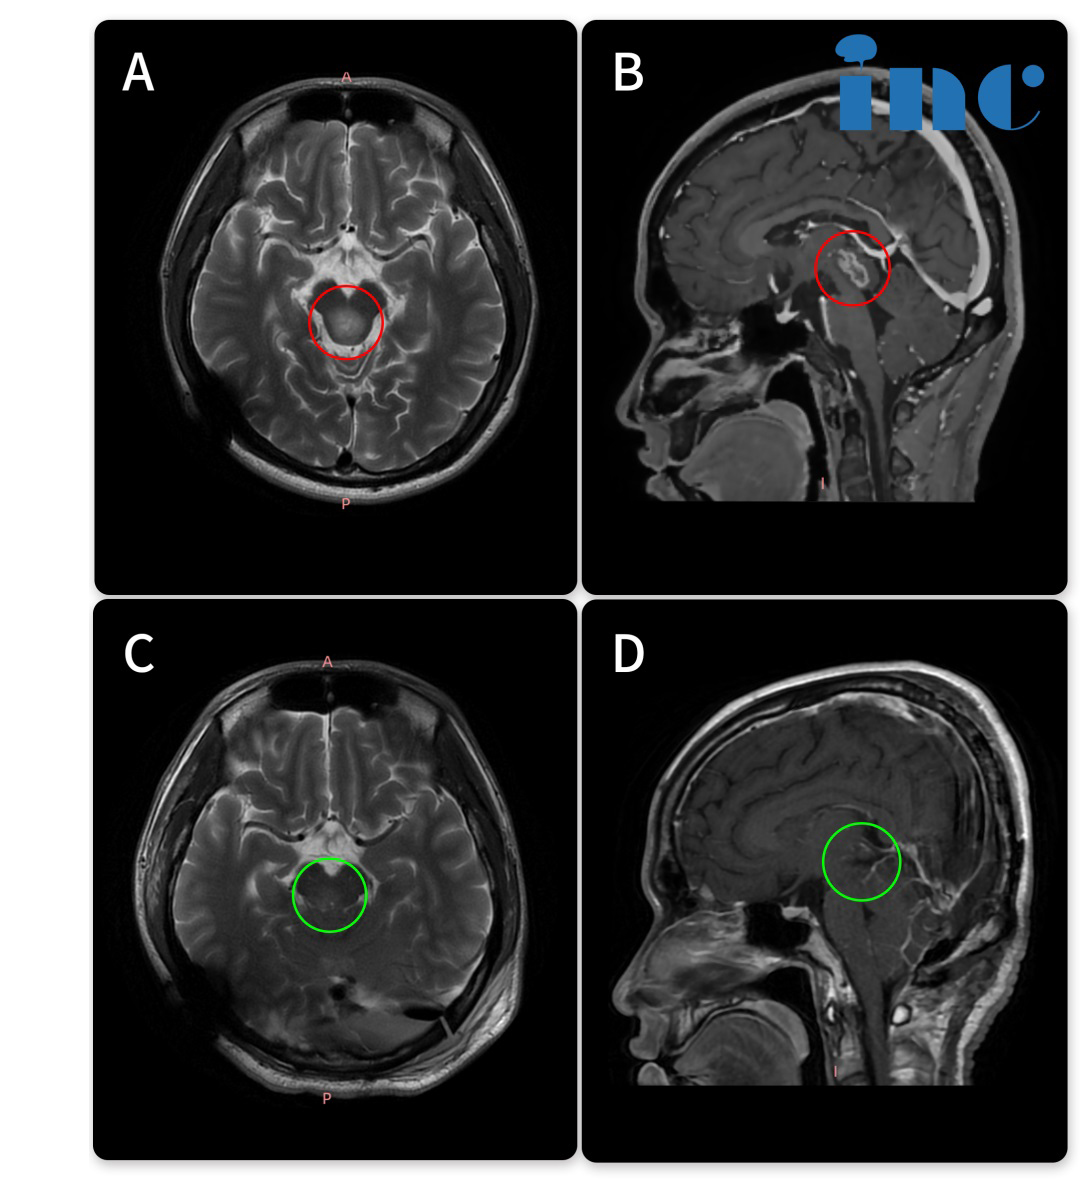

14岁的小永查出脑干胶质瘤,影像片子显示:脑干-中脑顶盖,伴有幕上脑室扩张积水,脑室及大脑实质已经受压变形。在与患者家属沟通中我们得知,小永2018年就出现过轻微头痛、头晕,去医院检查发现脑干肿瘤,并伴有梗阻性脑积水。小永的父亲咨询了很多专家。“每次都说毛细胞星形细胞瘤一般不长,观察就行,但是后来我然后一次去找他们的时候,我说症状太重,不行就做手术,他们然后和我说实话,因为做手术风险过大,所以说建议你观察……”这一拖就是2年多,孩子的病情越来越严重。

巴教授仔细研究小永的相关资料后表示:“已经有很明显的手术指征。我想知道为什么他还没有得到治疗,因为病变是从2018年就知道了。无论如何,我强烈建议不要给病人提供脑室腹腔分流术,因为这样一来,他将一直依赖于这个分流术。”小永的父母觉得再不能拖下去了,经过反复考量后,开始准备带孩子去德国找巴教授做手术,在INC协调和帮助下以较快的速度办完手续,不到一个月的时间内到达德国做上了手术。

手术结果令人欣喜,小永的肿瘤得到近全切除,病理结果为毛细胞型星形细胞瘤,这是一种预后较好的胶质瘤,全切或近全切后复发率低。

去年7月,术后已经过了1年半,我们对小永进行随访时得知他已经凭借的中考成绩,考入示范高中,其中体育成绩还获得了满分,完全看不出来曾经做过开颅脑干手术。